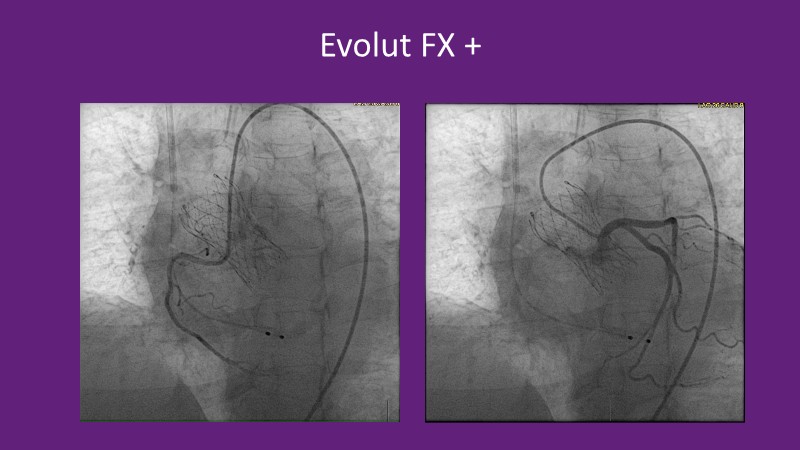

Don’t miss this PCR Tokyo Valves 2025 session replay, where leading experts share key techniques for simplifying and optimising TAVI procedures with the Evolut device. This session covers essential insights into safely performing procedures on patients with various anatomical types using the self-expandable valve, while emphasising the importance of long-term patient care and outcomes. Discover valuable strategies for surgical explantation of transcatheter aortic bioprostheses, coronary cannulation, and commissural alignment post-TAVR. Learn expert tips for streamlining procedures, such as semi-rapid pacing, using Dryseal long, and skipping pre-BAV to improve TAVI results. Watch now to stay ahead in the field!

- To understand how the self-expandable valve can be used to safely perform procedures on patients with various anatomy types